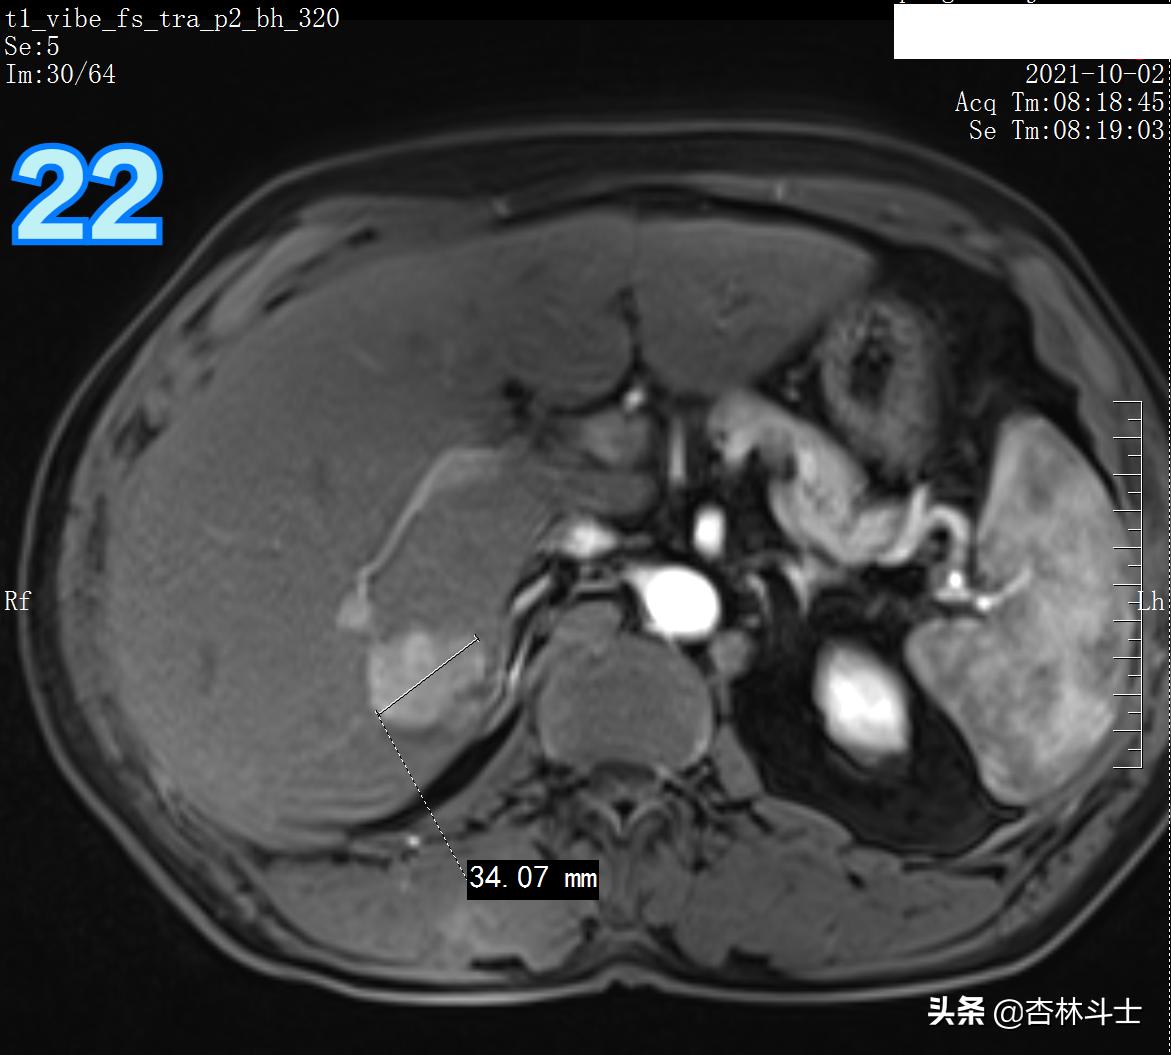

T1压脂动脉期

图21、22 动脉期病灶明显强化